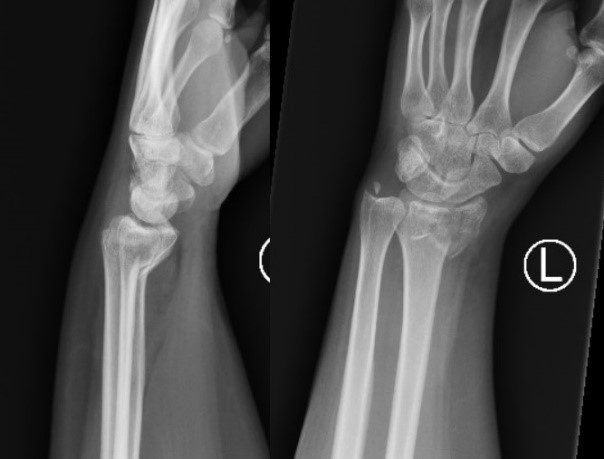

What fracture is this?

Smiths fracture

Colles Fracture